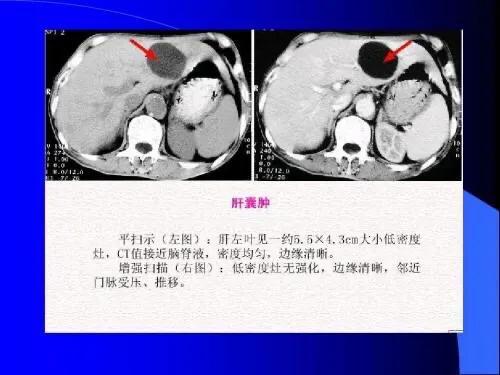

Ce type de kystes hépatiques, qui sont des lésions bénignes, ne présentent généralement pas de symptômes cliniques évidents et ne sont découverts qu'accidentellement lors d'une échographie ou d'un examen par tomodensitométrie, et seuls certains kystes de grande taille, qui provoquent des douleurs abdominales ou une gêne abdominale chez les patients, sont également généralement féminins.

En cas de kystes hépatiques inexpliqués, il est conseillé de se rendre à l'hôpital pour une tomodensitométrie améliorée du foie et de consulter un chirurgien hépatobiliaire pour mieux comprendre la situation. Il ne faut pas être comme le patient que j'ai rencontré dans l'article précédent, qui était déprimé tous les jours jusqu'à ce qu'il connaisse la vérité.

En général, si le kyste est petit et que le patient ne présente aucun symptôme, aucun traitement n'est nécessaire et un examen régulier suffit. Si un diagnostic clair a été posé, une échographie doit être réalisée tous les six mois environ afin d'observer tout changement dans le kyste.

L'examen de la fonction hépatique est généralement normal, l'examen échographique de la zone hépatique peut révéler plus d'un liquide de sécurité. La tomodensitométrie ou la scintigraphie nucléaire peuvent également vérifier la présence de kystes hépatiques multiples, en plus de déterminer que les kystes hépatiques multiples n'ont pas de lésions substantielles.